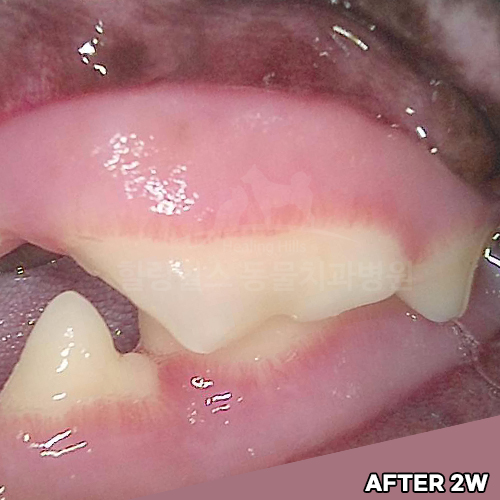

최고 난이도 강아지신경치료 - 꽉막힌 근관&치수괴사! 커다란 반려견치근단농양! 녹아내린 턱뼈! 치통으로 사나워진 모습! 강아지 신경치료 & 치주치료 한달 뒤 좋아졌어요!